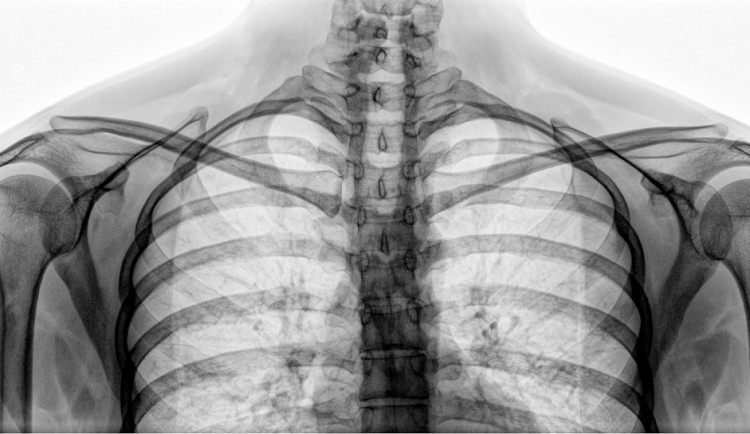

S prosbou o pomoc se na strážníky včera odpoledne obrátil lékař jedné z brněnských nemocnic. Když rentgenoval pacienta, osmačtyřicetiletý muž se najednou zvedl a utekl neznámo kam. Lékař přitom následně zjistil, že by muž mohl být v ohrožení života.

Medik tak neprodleně zavolal na tísňovou linku 156. Hlídka strážníků začala po zraněném muži pátrat a přibližně po hodině se jim ho podařilo najít.